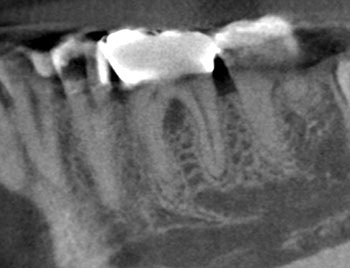

Case 3: A lateral lesion with a superficial crack

This patient presented for a second opinion after an endodontist recommended extraction for tooth #31 because of a VRF on its distal root. A deep isolated probing defect, a cervical sinus tract, the lateral position of the periradicular lesion and the prior placement of a full crown because of cracks in the tooth’s distal enamel marginal ridge likely contributed to the prior diagnosis of VRF.

A new diagnosis of previously treated and chronic apical abscess was made, but the possibility of a VRF was discussed with the patient. RCT was initiated. Internal examination of the pulp chamber reassuringly revealed that a crack on the distal wall of the pulp chamber did not extend to the pulpal floor. Treatment was completed in three visits using a calcium hydroxide intracanal medicament. Treatment and postoperative radiographs revealed a sharp dilaceration of the distal root, likely focusing the bony lesion toward the distal surface, not toward the root apex. Four months later, soft tissue and bony healing were confirmed.

Fig. 9: Preop PA.

Fig. 10: Preop CBCT.

Fig. 11: Preop probe.

Fig. 12: Recall PA.

Fig. 13: Recall CBCT.

Fig. 14: Recall probe.